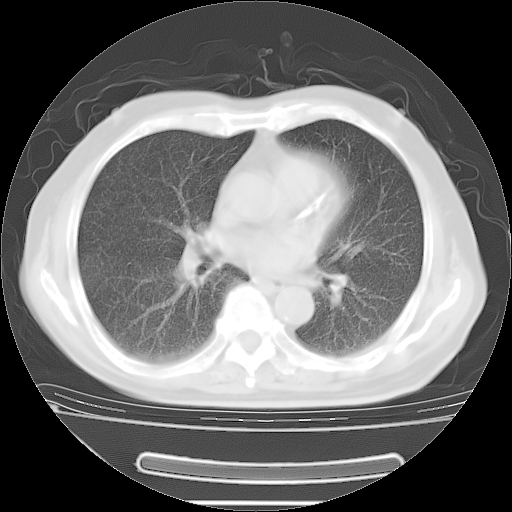

今天复查肺部CT,发现双肺广泛磨玻璃样改变。所以我把3月19日和5月9日相隔50天的肺部CT上传。请大家会诊。

2009年3月19日肺部CT片。

2009年3月19日肺部CT

5月9日肺部CT(在4月27日齐鲁医院肺部CT描述部分肺组织磨玻璃样改变,12天后肺组织广泛磨玻璃样改变)

大致读了系列胸部CT:纵隔窗无明显异常,肺窗:从4、27至今:主要是双肺中下野外带可见毛玻璃样改变,目前处于急性肺泡炎阶段,至于原因考虑1、结替组织或胶原血管性疾病所致?2、恶性疾病如恶组在肺部所致的表现或细支气管肺泡癌?3、药物或其它原因如肺蛋白沉着症所致肺泡炎目前不太可能?总之,明天就去请我院的呼吸科、感染科、血液科和临免专家会诊哈。